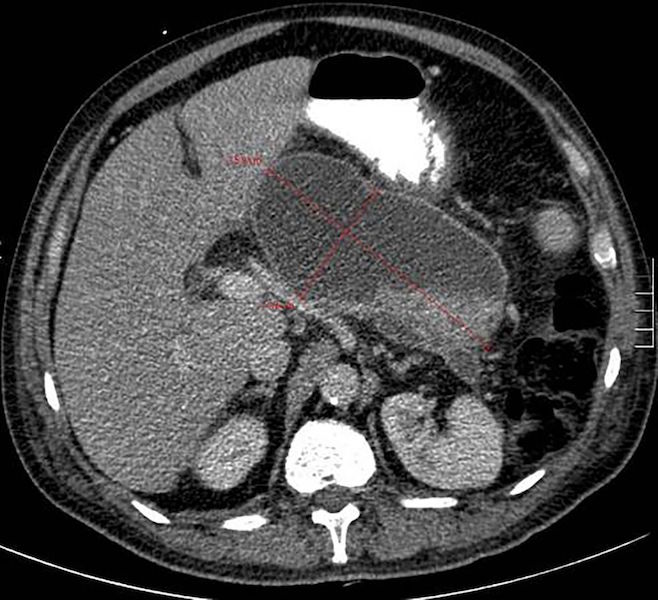

Pancreatite aguda

Necrose pancreática delimitada

Gut. 2017 Nov;66(11):2024-32; usado com permissão